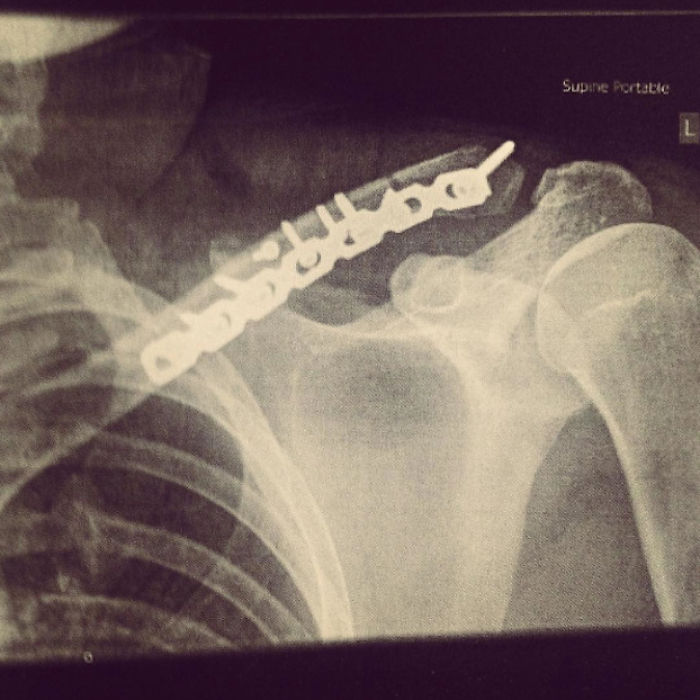

Three days later I was discharged, with a scar and some x-rays. The metal plate would hold my collarbone together while it healed, for the next year. Hospitals usually throw away the metalwork from surgeries like this, but I asked the surgeon to keep mine so that I could turn it into something. Scroll down to see the results!

Three days later I was discharged, with a scar and some x-rays that looked like this. The metal plate would hold my collarbone together while it healed, for the next year. It also only went off once at airport security – well done Berlin.

One year later the surgeon got out his scalpel and screwdriver, and unscrewed the metal from my bone

Hospitals usually throw away the metalwork from surgeries like this, but I asked the surgeon to keep mine so that I could turn it into something